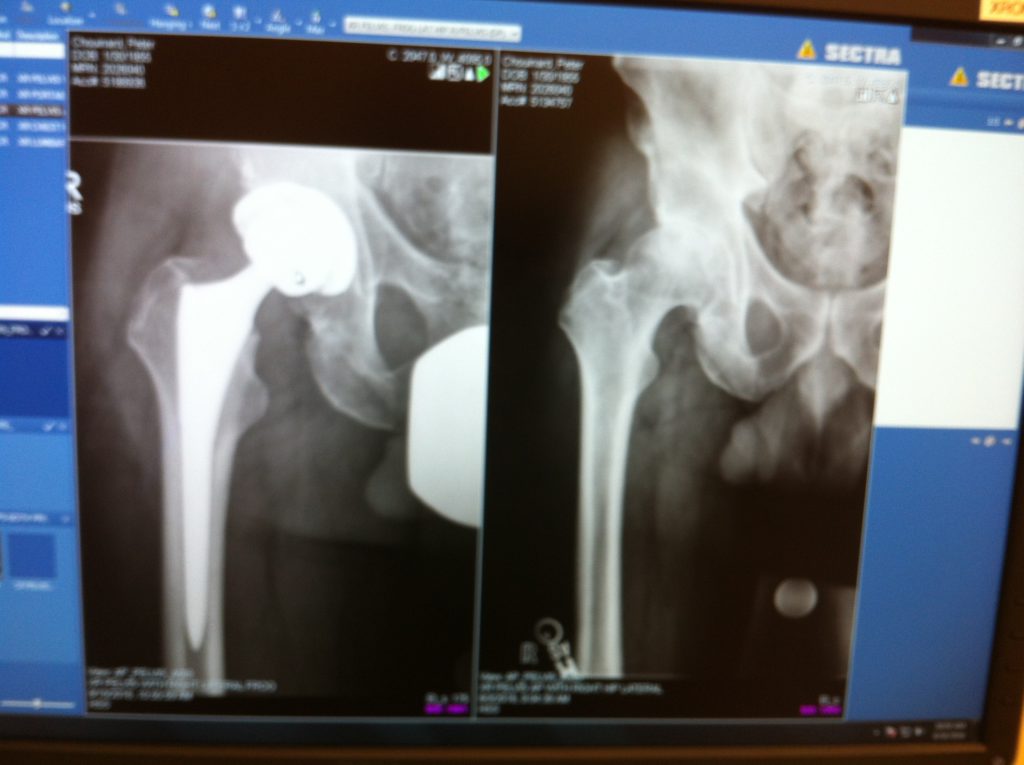

I was in pain in the top of my right foot, right knee and right groin for 1 year. I saw 2 surgeons in Suffolk county, one for my back and one for my hip. Neither wanted to operate saying they didn't know what to do. I had several steroid shots, tried acupuncture and final PT. During my discussion with the PT a women who had just had her hip replaced offered her miraculous experience (hip replacement) with Dr. Howard Rose. I went for a consultation with Dr. Rose and subsequently had the surgery (THR). My recovery was quick and ALL of my pain is completely gone and I am walking, running and playing racquetball as good or better than before my pain started. Doctor Rose thank you for giving my life back to me.

Hip Replacement